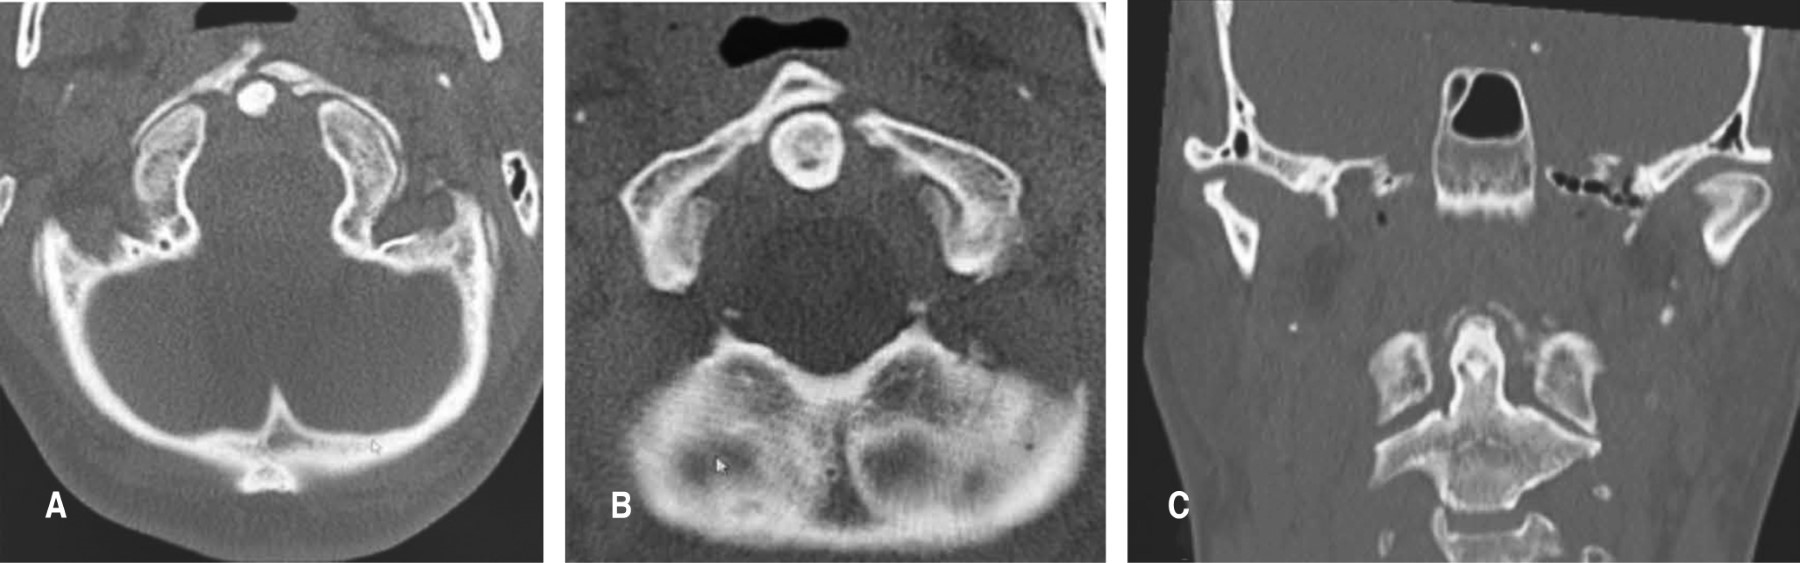

La hernia cervical traumática sin lesión ósea o articular asociada a mielopatía es una patología rara. Los casos reportados en la literatura tuvieron un diagnóstico tardío, secundario a hallazgos clínicos y radiológicos que pueden pasar desapercibidos. Habitualmente, el primer contacto con el paciente no lo realiza un cirujano especialista en columna. Se presenta el caso de un paciente masculino con traumatismo facial, que desarrolló una mielopatía cervical dos semanas después por hernia cervical traumática en C3-C4 sin lesión ósea, que no fue diagnosticada precozmente, posteriormente el paciente presentó alteración neurológica y requirió tratamiento quirúrgico para su descompresión y artrodesis anterior, con buenos resultados a los seis meses de seguimiento.

Figura 1